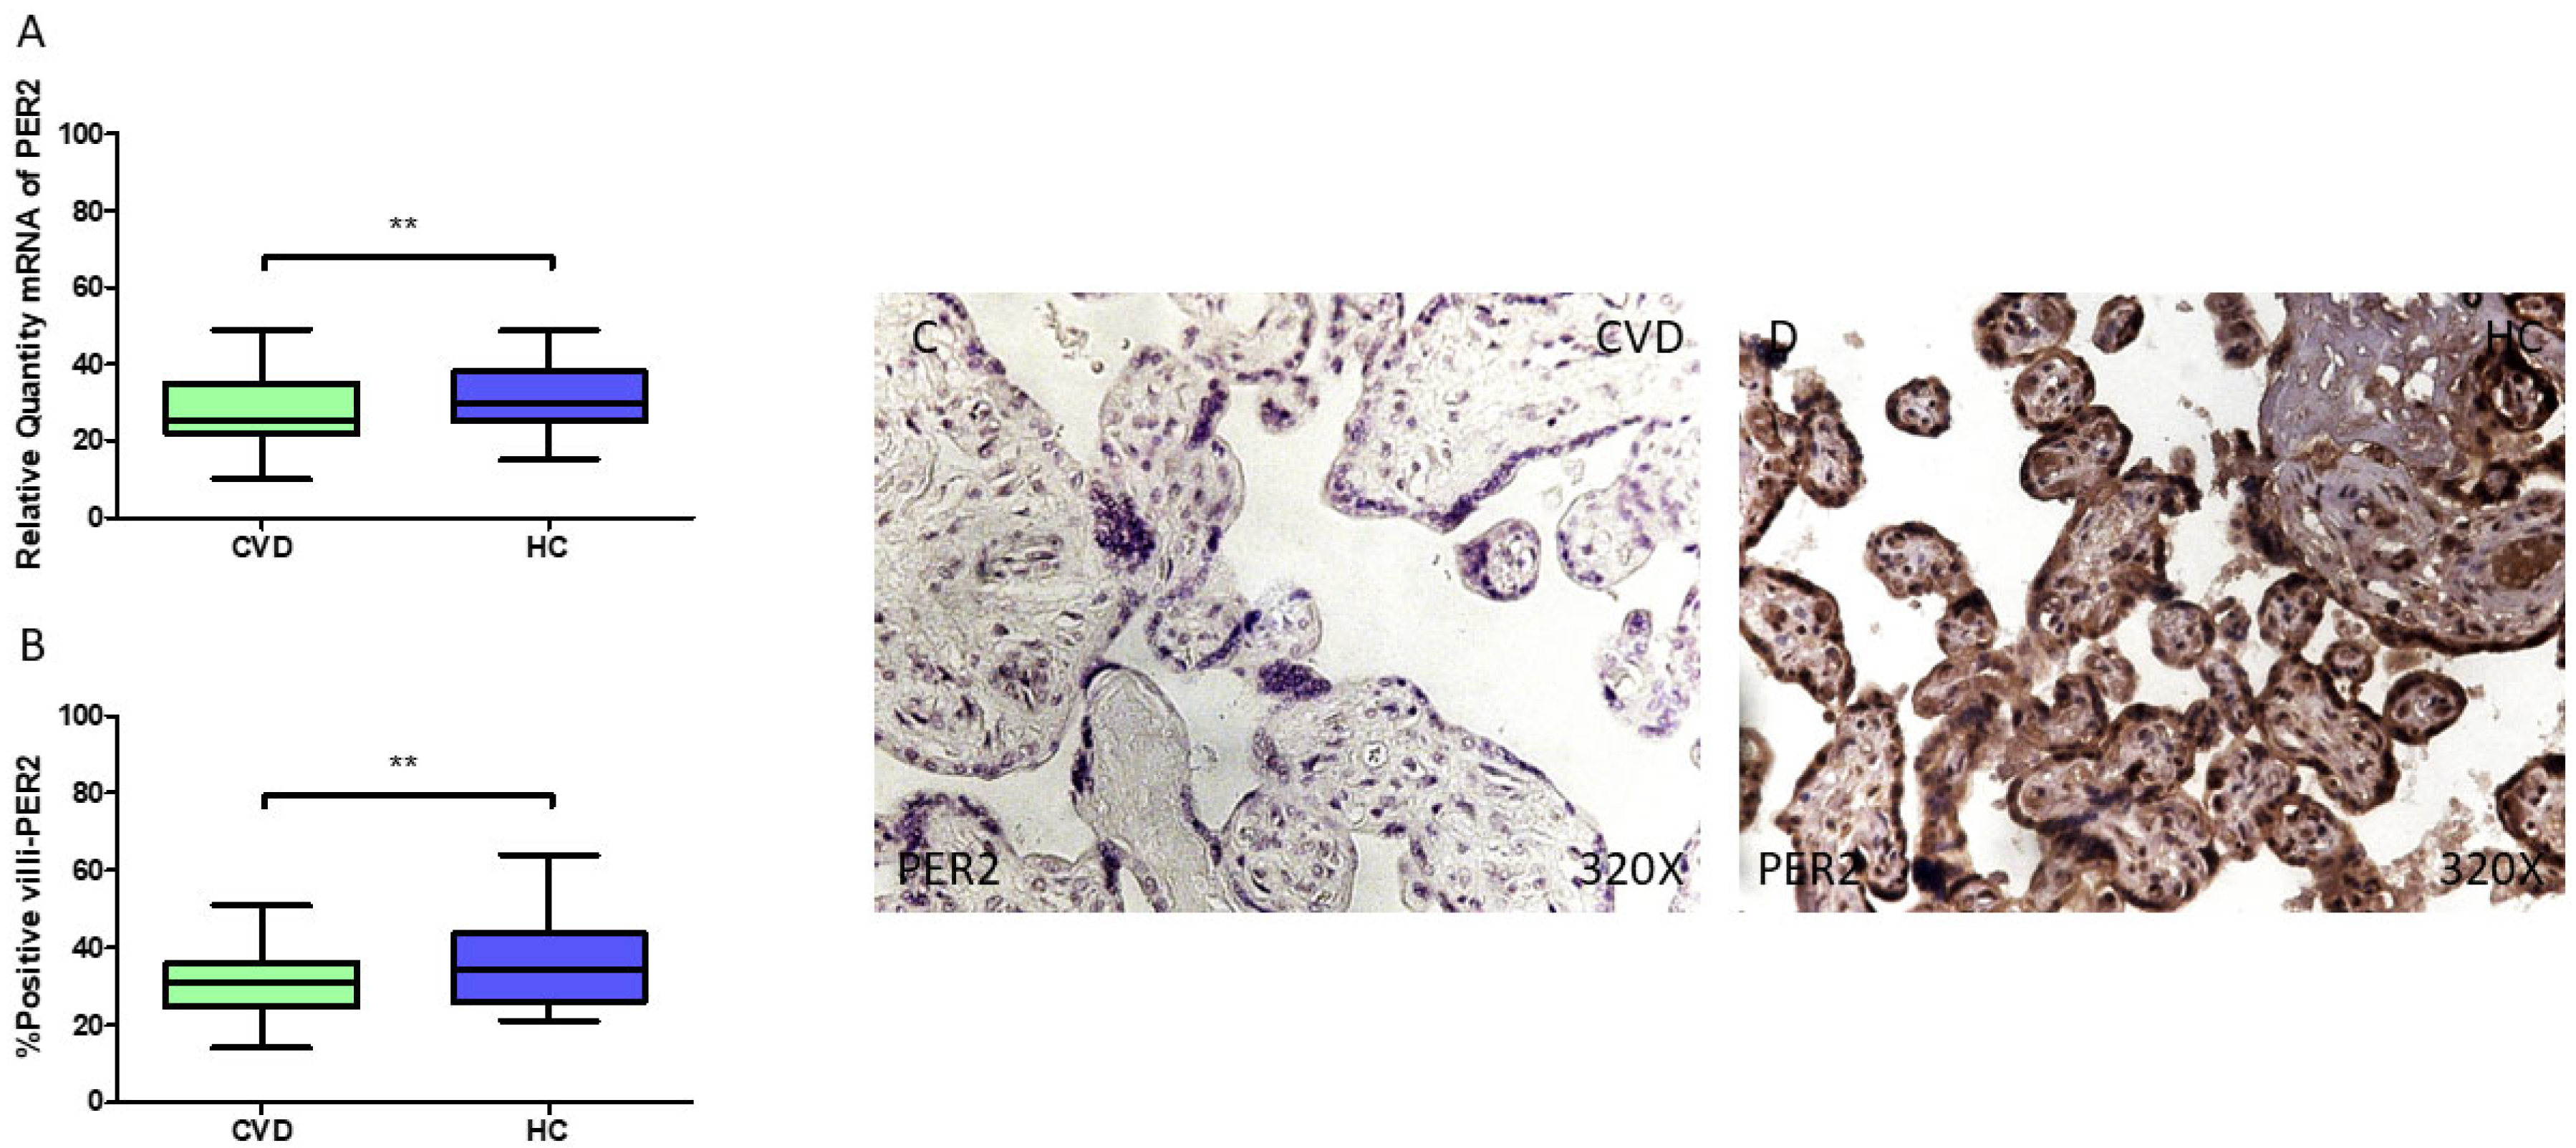

Lastly, our results demonstrate a statistically significant reduction in PER2 gene expression (RT-qPCR) in the placental tissue of pregnant women with CVD (** p = 0.0018; CVD = 25.408 [10.052–49.061], HC = 30.070 [15.062–48.878], Figure 5A). The histological analysis of the placental villi revealed a significant downregulation in Per2 protein expression (%) in the chorionic villi of women with CVD (** p = 0.0019; CVD = 31.000 [14.000–51.000], HC = 34.500 [21.000–64.000], Figure 5B). Per2 tissue expression was notably higher in all the placental villi of the HC women compared to the CVD group (Figure 5C,D).

Figure 5.

(A) PER2 mRNA expression levels in pregnant females who were diagnosed with CVD compared to HC group (** p < 0.01). (B) IRS scores assessing PER2 expression in placental tissue of women with CVD and without this condition (** p < 0.01). (C,D) Representative immunostaining images displaying Bmal1 expression in placental villi from CVD and HC samples.